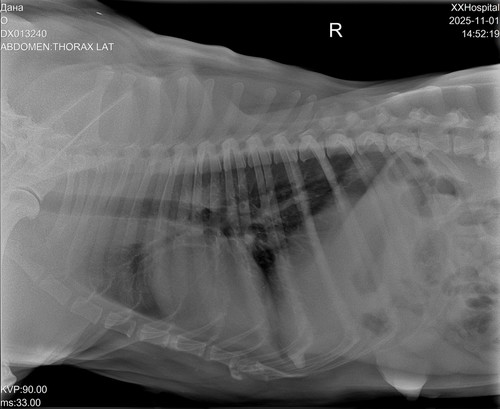

Дама в возрасте, лет 8-9. Вся в новообразованиях. В том числе раздут один сосок, откуда выделяется жидкость.